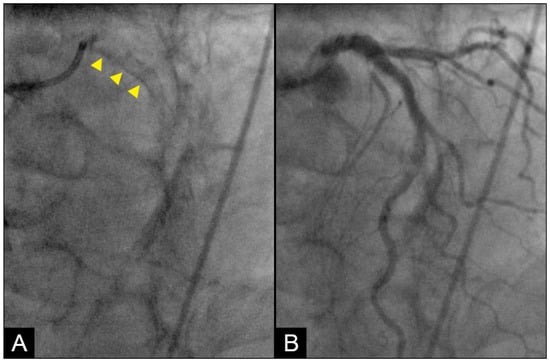

Conversely, in arteries affected by calcification, the vessel’s capacity to expand and contract becomes markedly compromised. The inability of the stiffened arterial wall to absorb the energy of the waves results in heightening the risk of endothelial microtears and further structural damage to the arterial wall (Figure 10) [26]. This phenomenon is particularly pronounced at the interface between calcified and non-calcified segments, which accounts for the frequent occurrence of new in-stent restenosis at the junction between the stent’s distal end and the arterial wall [27].

Additionally, this process elucidates the mechanism driving plaque cover rupture, which often arises at the junction between the plaque and adjacent normal tissue due to the impact of pressure waves on the mechanically unequal interface. As arterial stiffening progresses with calcification, it impedes the retrograde propagation of pressure waves [28]. This underscores the beneficial role of stenting in mitigating retrograde pressure wave effects on the new stent-scaffolded arterial wall. (Figure 11A–H).